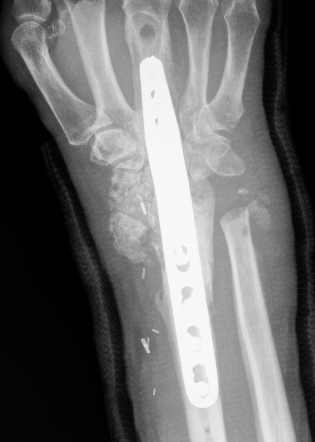

Flexor tendon rupture

Etiology

Plates distal to watershed mark

Prominent screws

Thicker plates

Incidence

Asadollahi et al J Orthop Traumatol 2013

- systematic review of flexor tendon rupture after plating of distal radius fractures

- 47 cases

- FPL 57%

- FDP to index finger 15%

Volar rim plates

Lari et al Eur J Orthop Surg Traumatol 2023

- systematic review of surgical treatment of volar rim fractures

- 26 studies and 600 patients

- implant removal 22%

- flexor tendon irritation 6%